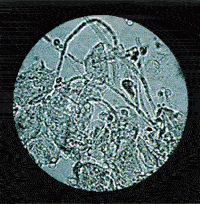

Levaduras y pseudomicelios

de Candida spp. en flujo vaginal